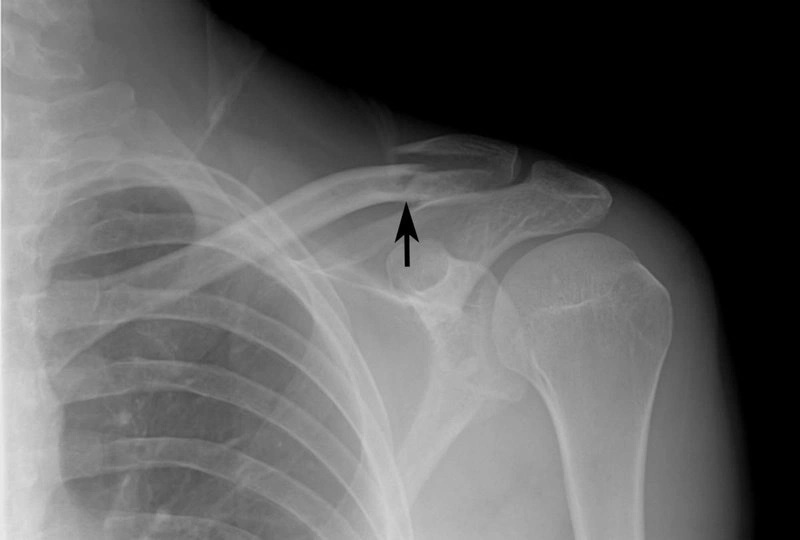

Xương quai xanh (xương đòn) là một đoạn xương dài, nằm ngang ở phần trên của lồng ngực, nối giữa xương ức và xương bả vai. Đây là một trong những xương quan trọng giúp hỗ trợ cử động vai và duy trì cấu trúc cơ thể.

Gãy xương quai xanh thường xảy ra do các tác động lực mạnh vào vùng vai hoặc ngực. Một số nguyên nhân phổ biến bao gồm:

Thông thường, gãy xương quai xanh không trực tiếp đe dọa tính mạng, nhưng nếu không được điều trị đúng cách, nó có thể gây ra các biến chứng nghiêm trọng như: